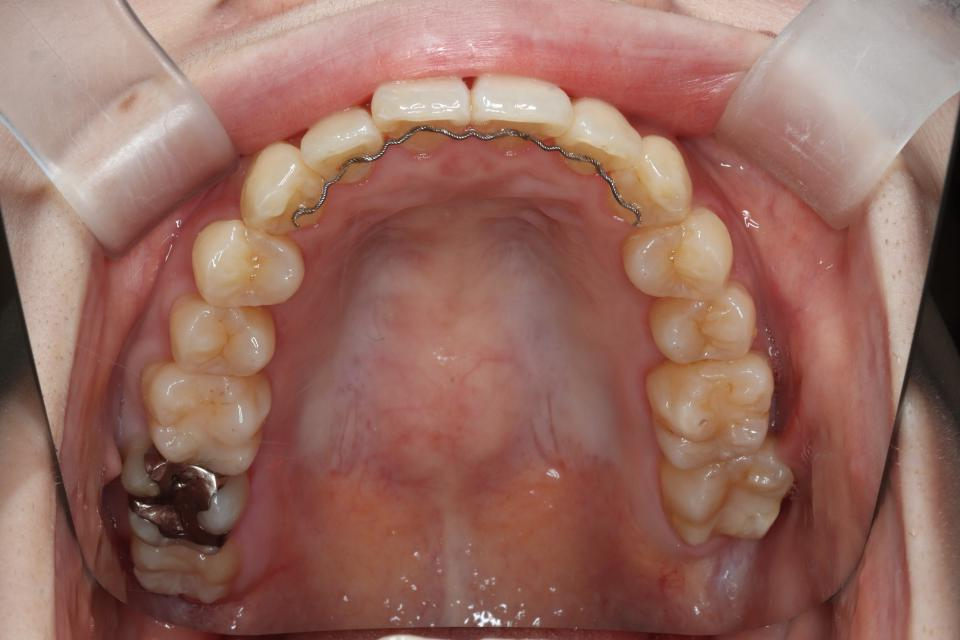

マウスピース型矯正装置による部分矯正治療

矯正治療前

矯正治療後

20代女性です。

上の前歯が2本出ているのが気になると当院に来院されました。

部分的な矯正を希望され、

奥歯の嚙み合わせにも大きな異常はなかったため、

取り外し可能なマウスピース矯正で治療をおこないました。

きれいに並びきるよう歯のやすりがけ(IPR)をしています。

歯を動かす治療は終了し、

現在は上下の前歯の裏側に後戻り防止の針金(FIX)を貼り、

定期的なチェックをしています。